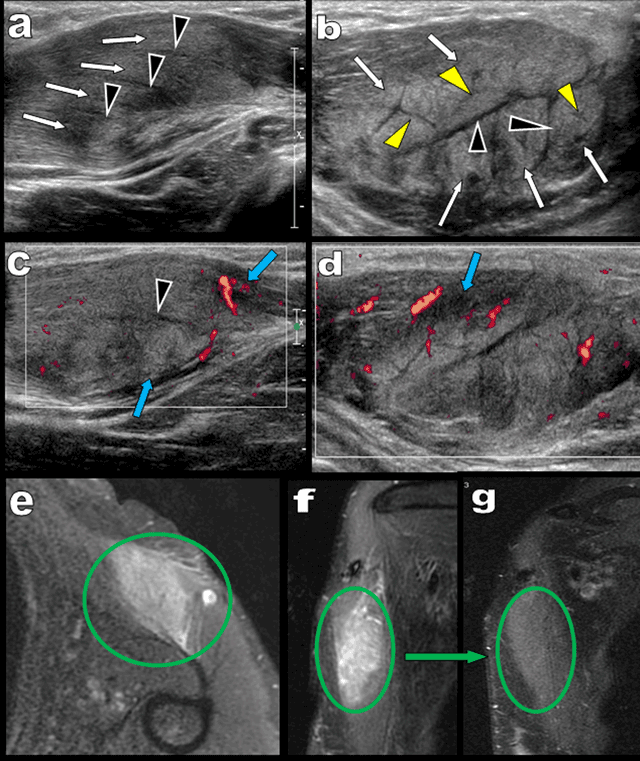

Muscular ultrasound (US) was required for a 53-year-old woman presenting with a rapidly growing firm and painless mass developing near the humeral insertion of the left pectoralis major. Longitudinal US (Figure 1a and 1c) showed intact but swollen hyperechoic muscle fascicles (white arrows) dissociated by vascularized hypoechoic bands (black arrowheads). Transverse US (Figures 1b, 1d and 2a) identified a subtle additional network of fine hypoechoic bands (yellow arrowheads) within the swollen muscle fascicles. Vascularized hypoechoic bands were also visible in the perimuscular fascia (blue arrows on Figure 1c and 1d). The typical “dry cracked mud” pattern of proliferative myositis (PM) was recognized (Figure 2b) and confirmed by fat suppressed T2 weighted MRI imaging (Figure 1e) showing focal hyperintense muscular enlargement. Magnetic resonance imaging (MRI) views perpendicular to the long axis of the muscle also found intact muscular fascicles within the area of hyperintensity (Figures 1f and 2c). The patient was very reluctant toward biopsy, so careful watch-and-wait follow-up was proposed. Control MRI performed after eight weeks confirmed complete healing (Figure 1g).

Figure 1